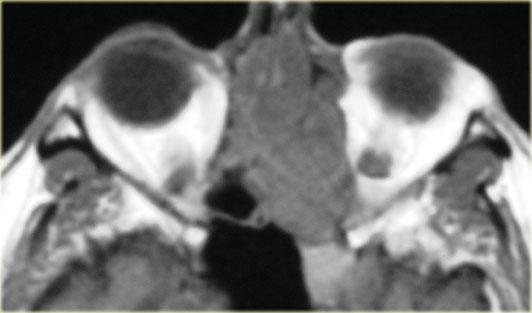

Bên trái là chuỗi xung T1W mặt phẳng axial, bên phải là chuỗi xung T2W mặt phẳng coronal.

Có bất thường ở bên trái, nhưng ở mức độ ít hơn cũng có ở bên phải.

Hãy cố gắng xác định các cấu trúc nào bị tổn thương.

Các mũi tên vàng chỉ vào ống lệ mũi.

Túi lệ kết nối với ống lệ, sau đó dẫn lưu vào ngách mũi dưới.

Bên trái có phù nề mô mềm quanh hốc mắt trước vách ngăn.

Trên hình ảnh coronal, có tín hiệu cao hai bên tại vị trí nối giữa ống lệ mũi và túi lệ, gợi ý ổ dịch.

Bên trái cũng có phù nề mô xung quanh.

Chuỗi xung T1W sau tiêm thuốc tương phản từ, mặt phẳng axial và coronal.

Ở phía ngoài ống lệ mũi hai bên, có các ổ dịch hiện nay cho thấy hình ảnh ngấm thuốc ngoại vi.

Các hình ảnh bổ sung (chuỗi xung T2W) cho thấy bệnh lý niêm mạc xoang hàm phải và mức dịch trong xoang hàm trái, ngoài ra còn có bệnh lý xoang sàng và xoang bướm lan rộng.

Bệnh nhân này bị viêm xoang cấp tính có biến chứng viêm mô tế bào hốc mắt và viêm túi lệ kèm áp xe.

Hẹp ống lệ mũi do bẩm sinh hoặc do viêm là yếu tố nguy cơ dẫn đến viêm túi lệ.